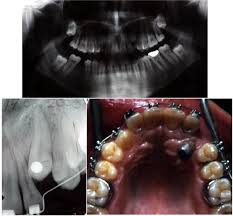

Tads Assist Forced Eruption Of Upper Labially Impacted Canine Case Report

Tads Assist Forced Eruption Of Upper Labially Impacted Canine Case Report from www.oatext.com

This facilitates eruption and orthodontic traction. The difference in time required for the two techniques was statically significant (p = 0.000). 5.3.1 open exposure 5.3.2 closed eruption technique 5.3.3 open versus closed eruption techniques. Patients perception of recovery after exposure of impacted teeth: If a canine is associated with severe resorption of the root of the incisor, an open exposure is not indicated since it endangers the vitality and existence of the incisor. If the crown is positioned mesial to the lateral incisor, a closed technique for the pataltal eruption of canine. Two techniques for exposing palatal canines are routinely used in the uk: The mean surgical time table 3 for open eruption technique was 22.31 ± 1.98 min as compared to 30.87 ± 2.38 min to closed eruption technique.

Chaushu s(1), becker a, zeltser r, vasker n, chaushu g. Preorthodontic exposure and autonomous eruption The open exposure technique consists of surgical removal of the tissue covering the tooth, leaving it exposed to the oral cavity. Given the reported success of forced eruption, the technique requires… continue reading The present study provides information to patients and clinicians. Duration of surgical procedure (in min) click here to view Dr vanarsdall recommends open exposure with a repositioned gingival flap (pediculated connective tissue graft) above the impacted canine. Apically position flap the goal is to choose a technique that exposes the canine within the a zone of keratinized mucosa without involvement of the cementoenamel junction 27. The open eruption technique may be performed in two different ways, as described below. If the canine crown is positioned distal to the mesial aspect of the lateral incisor, an open technique is performed. Forced eruption can preserve the natural root system and related periodontal architecture, resulting in years of additional service for the patient. Open eruption through a window; In this technique sufficient space.